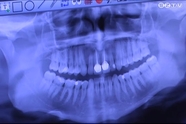

Modern orvosi eszközökkel felszerelt ez a fogászati rendelő, amit több mint egy évig önerőből újított fel a tulajdonosa. Az átalakítások során került ide ez a korszerű fogorvosi szék is, mondja a szakorvos.